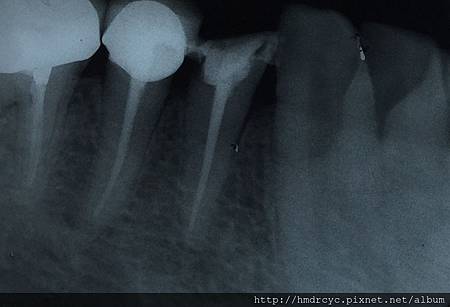

1. 打開神經管 去除蛀牙 舊的填補物 修整牙齒外型

3. 擴大神經管 完全去除殘留牙髓組織

4. 神經管修型

6. 牙膠緻密封填